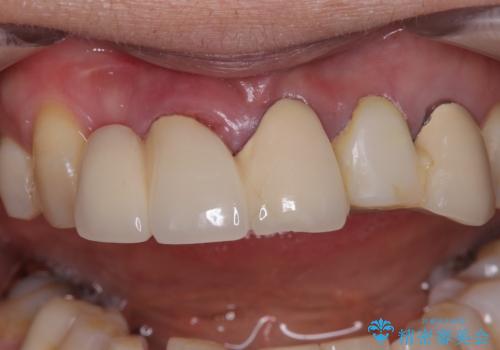

不具合の多い前歯 オールセラミックブリッジ治療

- 前歯のブリッジに違和感を感じるとのことで来院された患者様です。

受け口を無理やりブリッジで改善したことで、支台歯の1本は歯根が破折しており抜歯が必要な状態でした。

根管治療がされている歯の一部には根尖部の違和感があり、根管治療が必要と判断されました。

抜歯および根管治療を実施した後にオールセラミッククラウンにて補綴することとしました。

歯肉ラインの改善には歯周外科処置が必要でしたが、大きく笑っても歯肉ラインが唇に隠れるとのことで、外見の改善はせず、清掃性の大会ブリッジを装着いたしました。